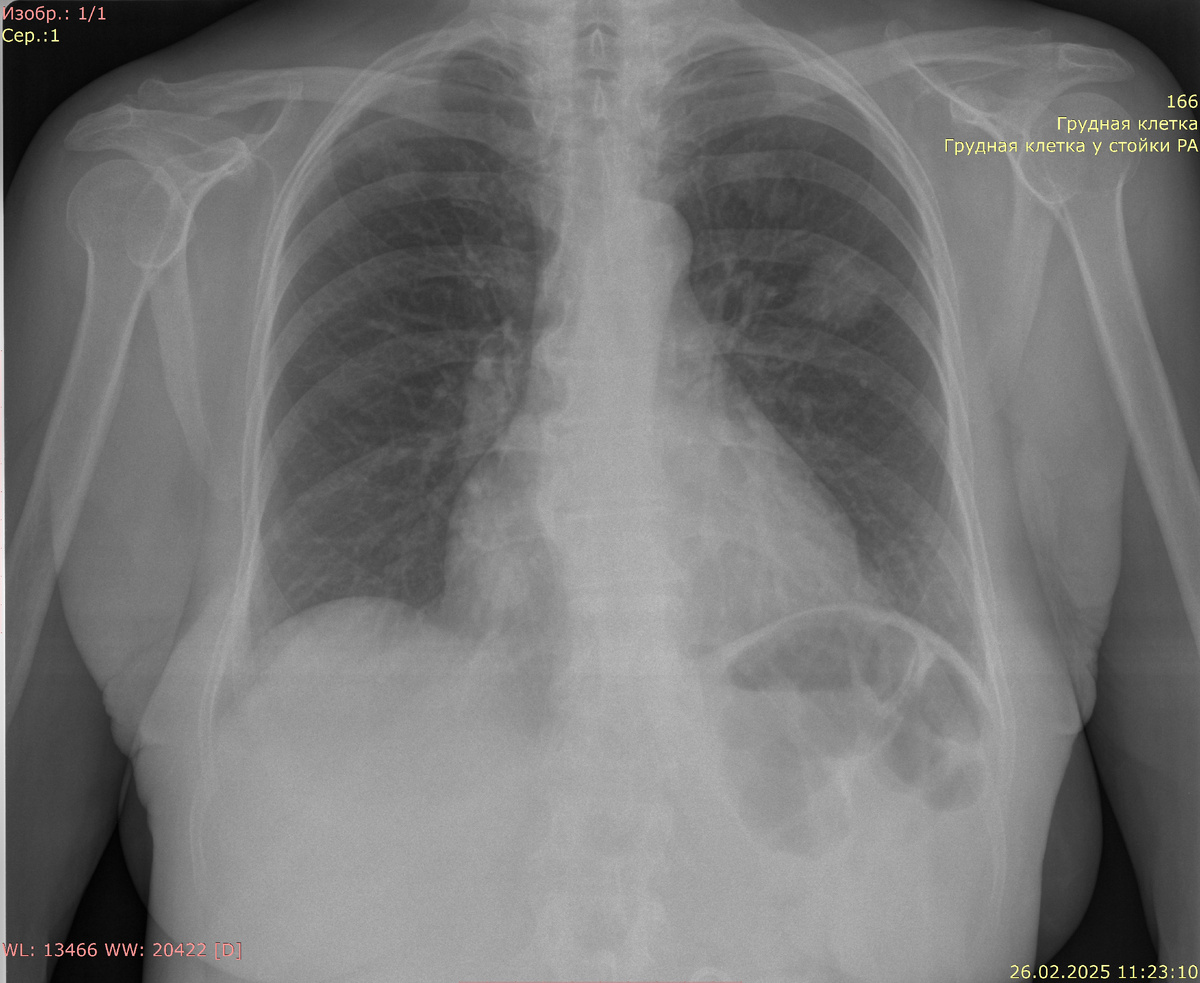

Рентгенография органов грудной клетки в прямой проекции:

Видимые дыхательные пути проходимы. Тень средостения не смещена, не расширена. Корни легких четкие, структурные, не расширены. В среднем поле левого легкого округлая тень с четкими границами диаметром 27 мм, связано "дорожкой" с корнем легкого. Такие же образования поменьше в верхних легочных полях обоих легких. Инфильтративных изменений в легких нет. Синусы свободны. Костно-деструктивных изменений нет. Свободный газ не определяется.

Заключение: образования обоих легких (метастазы?). Уместно дообследование. Гидроторакса, пневмоторакса, пневмонии нет